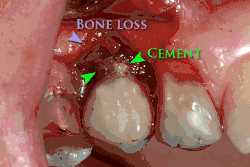

Cement peri-implantitis

Dental cement under the gingiva causes peri-implantitis and implant failure.

Beyond the possibility of mechanical failure[98] which may be due to poor prosthetic fitment, wear and tear, or user-induced actions such as bruxism, dental implants are also subject to peri-implant mucositis and peri-implantitis, where gum tissue and bone mass around the implant are resorbed, and the implant gradually becomes loose, and has to be removed.[99][100] In addition, although titanium is generally well tolerated by the body, there have been cases where the build-up of titanium particles released by the implant may cause systemic inflammatory response.[101] Because there is no dental enamel on an implant, it does not fail due to cavities like natural teeth. While large-scale, long-term studies are scarce, several systematic reviews estimate the long-term (five to ten years) survival of dental implants at 9398 percent depending on their clinical use.[15][16][17] During initial development of implant retained teeth, all crowns were attached to the teeth with screws, but more recent advancements have allowed placement of crowns on the abutments with dental cement (akin to placing a crown on a tooth). This has created the potential for cement, that escapes from under the crown during cementation to get caught in the gingiva and create a peri-implantitis (see picture below). While the complication can occur, there does not appear to be any additional peri-implantitis in cement-retained crowns compared to screw-retained crowns overall.[102] In compound implants (two stage implants), between the actual implant and the superstructure (abutment) are gaps and cavities into which bacteria can penetrate from the oral cavity. Later these bacteria will return into the adjacent tissue and can cause periimplantitis.